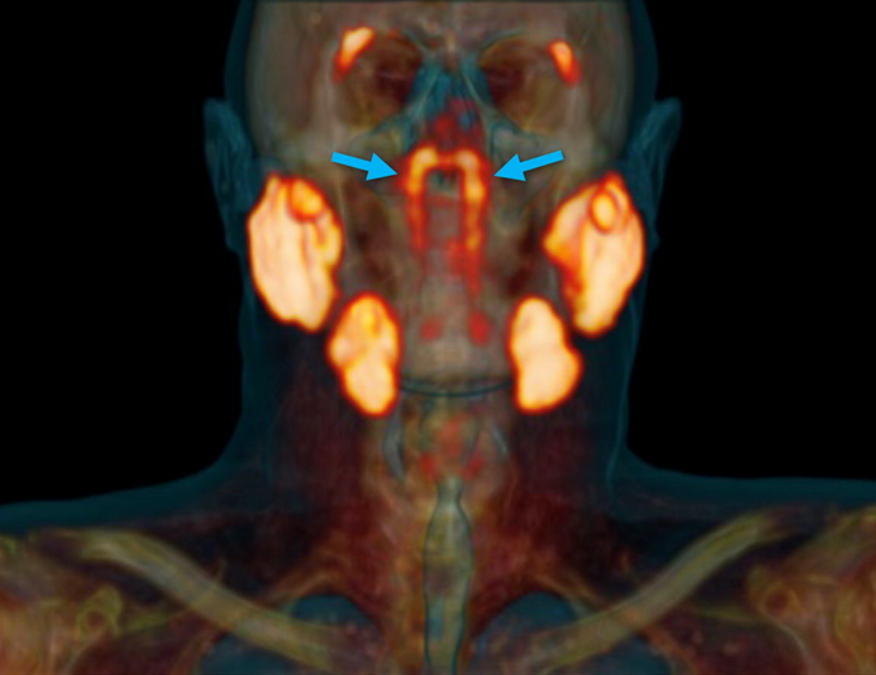

На обнаруженные железы указывают синие стрелки (фото: Valstar et al., Radiotherapy and Oncology, 2020)

Новый орган был найден во время сканирования PSMA PET/CT. Обычно, в сочетании с инъекциями радиоактивной глюкозы этот диагностический инструмент выявляет опухоли в организме. В данном случае, однако, обнаружилось нечто совершенно иное, расположившееся в задней части носоглотки и довольно долгое время скрывавшееся.

Новое открытие, сделанное командой Фогеля, показывает, что обнаруженные железы намного больше, чем те, которые можно увидеть только под микроскопом. Ученые предполагают, что это еще один набор основных слюнных желез.